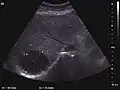

Regenerative nodule (CEUS). One can see the hypovascular pattern of the solid nodule, with a size <10 mm.

These lesions are well defined, with isoechoic or hypoechoic appearance and sizes less than 1 cm. They are high in numbers and have a more or less uniform distribution, involving all liver segments. They can crowd resulting in large pseudo tumors. At Doppler examination, these nodules have no circulatory signal. CEUS exploration is indicated when a nodule is different against the general pattern of restructured liver either by different echogenity or by a different size than the majority of nodules. During the arterial phase, the signal is weak or absent. During the portal venous and late phase, the appearance is persistently isoechoic.

Generally, RN is not distinct from the surrounding parenchyma. CEUS examination is useful to exclude an active lesion at the moment of exploration but does not have absolute prognostic value; therefore the patient should be periodically examined at short intervals. Correlation with clinical status and AFP measurements is required.